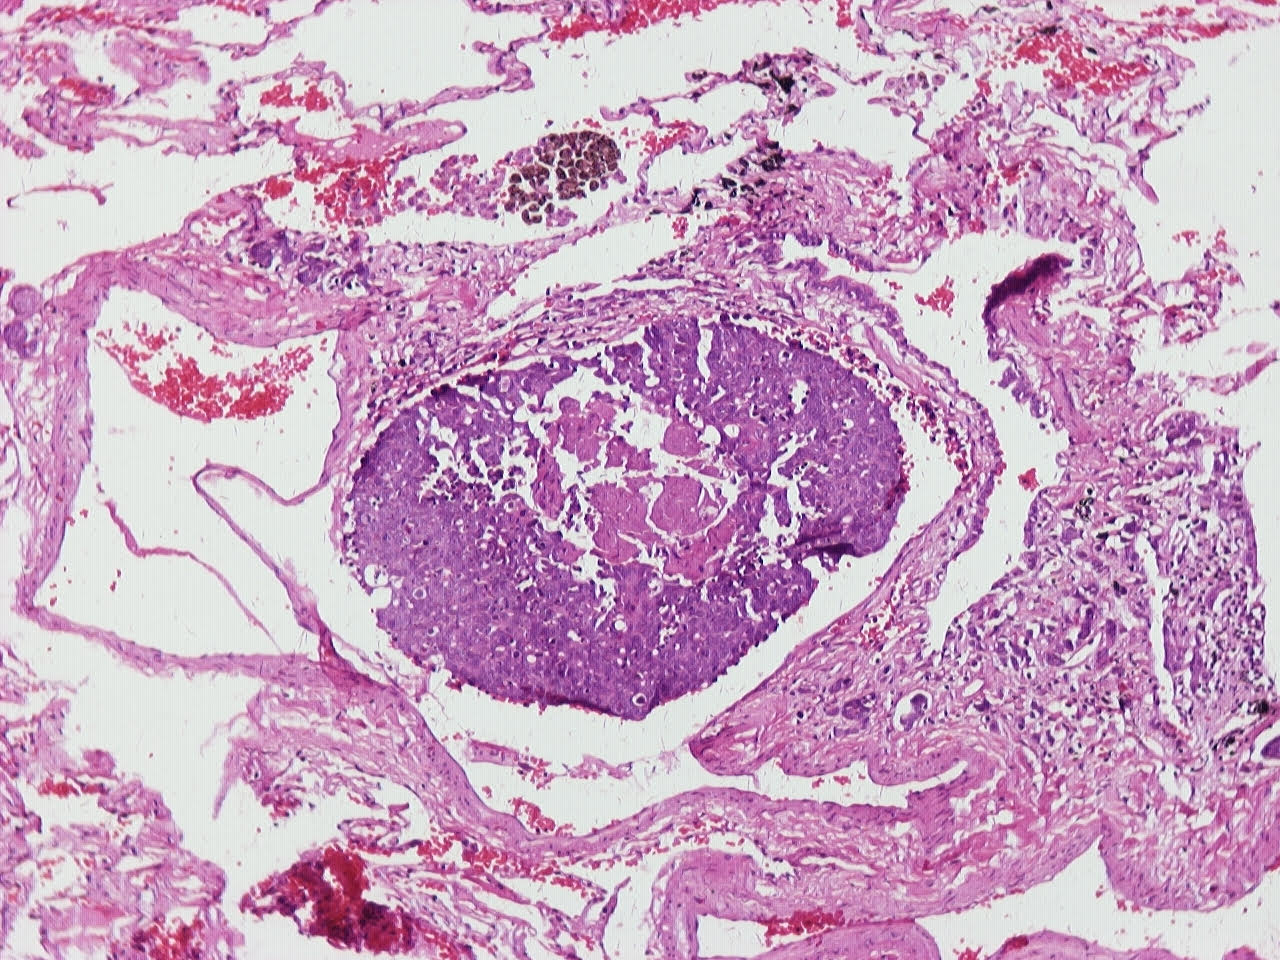

- Neuroendocrine organoid architecture may include nesting with peripheral palisading, anastomosing trabeculae and rosette-like structures (Mod Pathol 2022;35:36)

- > 10 mitoses/2 mm2, extensive / geographic necrosis

- Large cells (~3x size of small cell carcinoma) with abundant amphophilic cytoplasm, intercellular membranes, nuclear pleomorphism, variably coarse, granular or vesicular chromatin with prominent nucleoli (Transl Lung Cancer Res 2020;9:860, Mod Pathol 2022;35:36)

Microscopic (histologic) images

Contributed by Ioanna Abba Nteka, M.D., Aggeliki Cheva, M.D., Ph.D., Antonia Loukousia, M.D., Roseann Wu, M.D., M.P.H. and Kyriakos Chatzopoulos, M.D., Ph.D.